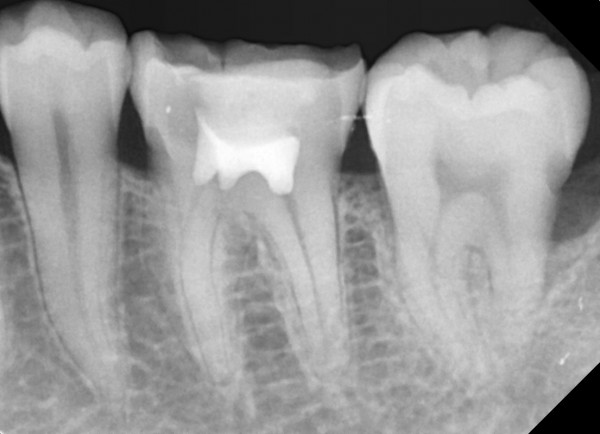

충치치료&신경치료 하루에 끝나는 신경치료

c36d6f431fa4d39e6efca10cb66686a2_1767329043_0796.jpg